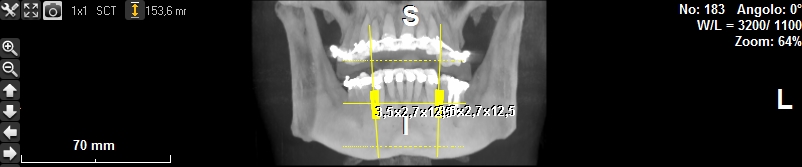

Progettazione virtuale / chirurgia guidata Un esempio della progettazione 3D di un intervento di posizionamento implantare SENZA BISTURI. Photogallery: